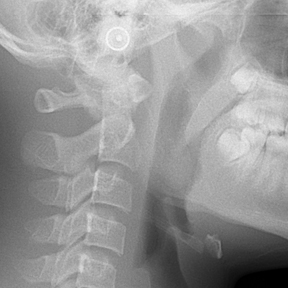

얼굴 골격의 성장에 문제가 있는지를 파악하기 위한 적절한 시기는 초등학교 입학 전인 6-7세경입니다. 이때는 유치에서 영구치로 교환되는 시기로서 부정교합 여부가 결정되는 중요한 시기이므로 이 시기를 잘 관찰하여 부정교합을 예방하는 것 또한 중요합니다. 교정의 정확한 시기는 6개월 간격으로 치과에 정기적으로 내원하여 성장 분석을 받은 후 결정하는 것이 좋습니다.